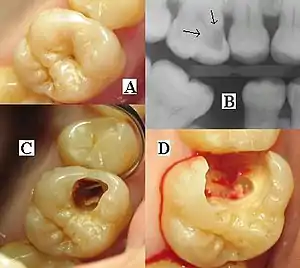

| Destruction of a tooth by dental caries and disease. | |

A person experiencing caries may not be aware of the disease.[13] The earliest sign of a new carious lesion is the appearance of a chalky white spot on the surface of the tooth, indicating an area of demineralization of enamel. This is referred to as a white spot lesion, an incipient carious lesion or a "microcavity".[14] As the lesion continues to demineralize, it can turn brown but will eventually turn into a cavitation ("cavity"). Before the cavity forms, the process is reversible, but once a cavity forms, the lost tooth structure cannot be regenerated. A lesion that appears dark brown and shiny suggests dental caries were once present but the demineralization process has stopped, leaving a stain. Active decay is lighter in color and dull in appearance.[15]

As the enamel and dentin are destroyed, the cavity becomes more noticeable. The affected areas of the tooth change color and become soft to the touch. Once the decay passes through enamel, the dentinal tubules, which have passages to the nerve of the tooth, become exposed, resulting in pain that can be transient, temporarily worsening with exposure to heat, cold, or sweet foods and drinks.[16] A tooth weakened by extensive internal decay can sometimes suddenly fracture under normal chewing forces. When the decay has progressed enough to allow the bacteria to overwhelm the pulp tissue in the center of the tooth, a toothache can result and the pain will become more constant. Death of the pulp tissue and infection are common consequences. The tooth will no longer be sensitive to hot or cold, but can be very tender to pressure.

The presentation of caries is highly variable. However, the risk factors and stages of development are similar. Initially, it may appear as a small chalky area (smooth surface caries), which may eventually develop into a large cavitation. Sometimes caries may be directly visible. However other methods of detection such as X-rays are used for less visible areas of teeth and to judge the extent of destruction. Lasers for detecting caries allow detection without ionizing radiation and are now used for detection of interproximal decay (between the teeth).

Primary diagnosis involves inspection of all visible tooth surfaces using a good light source, dental mirror and explorer. Dental radiographs (X-rays) may show dental caries before it is otherwise visible, in particular caries between the teeth. Large areas of dental caries are often apparent to the naked eye, but smaller lesions can be difficult to identify. Visual and tactile inspection along with radiographs are employed frequently among dentists, in particular to diagnose pit and fissure caries.[89] Early, uncavitated caries is often diagnosed by blowing air across the suspect surface, which removes moisture and changes the optical properties of the unmineralized enamel.